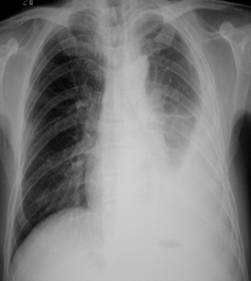

照片名称:胸腔积液

照片名称:左侧胸腔积液

照片名称:大量胸腔积液